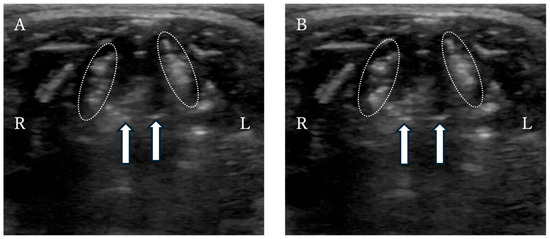

Tracheal stent fracture is a major complication of endoluminal tracheal stent (ELS) for canine tracheal collapse, and optimal management strategies remain unclear. A 4-year-old Yorkshire Terrier presented with respiratory distress caused by complete ELS fracture. Imaging and bronchoscopy revealed intraluminal protrusion of fractured stent segments, ventral tracheal cartilage invagination, and marked luminal deformation. A polypropylene linear prosthesis (PLLP) was selected as an external tracheal support. Its continuous band-like structure allowed broad and uniform reinforcement of the tracheal wall and redistribution of mechanical stress. PLLP placement successfully restored a near-normal tracheal contour and stabilized the fractured stent without introducing additional intraluminal material. Postoperative bronchoscopy confirmed improved tracheal patency, and no further deformation or stent damage was observed despite several months of altered airway dynamics associated with laryngeal paralysis. This case suggests that PLLP may represent a valid surgical option for managing tracheal stent fracture in dogs. Full article